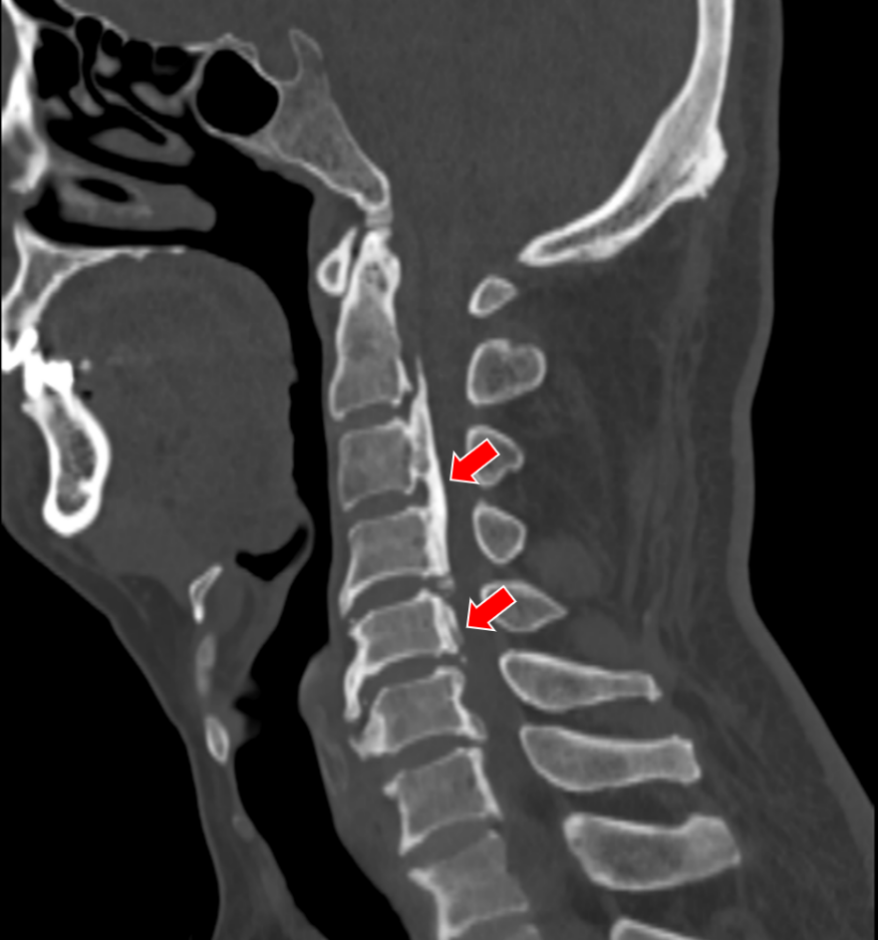

(颈椎CT提示患者C5-6的椎间盘突出棒骨性狭窄)

在沈阿姨术后第三天,其表姐王阿姨也在她的推荐下来住院了。王阿姨的症状和沈阿姨几乎一样,在住院的前1个月,她右上肢的疼痛感突然加剧,病变的节段是C5-6,看到表妹的手术效果如此显著,她决定也来做手术。

(C5-6 ACDF术,患者手术疗效确切)